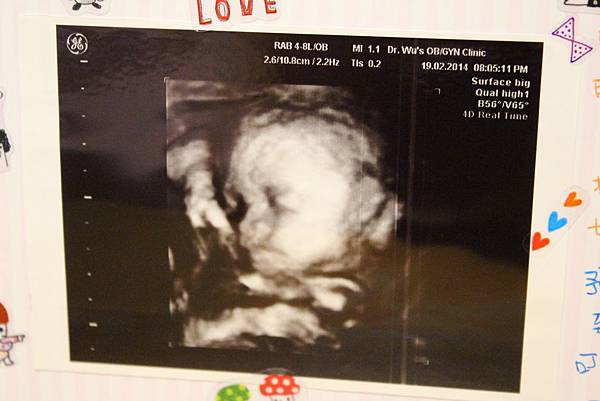

• 【孕期】為什麼肚子裡有外星人

IMG_3872.JPG

時間很快又過了一個月

終於到了第二次產檢的日子